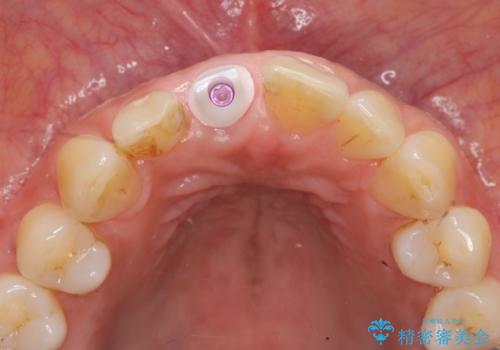

- 50万円(ストローマンインプラント・骨造成・ジルコニアカスタムアバットメント・ジルコニアクラウン)費用は治療当時の料金となります

前歯のインプラント治療は適切に行えば、ブリッジのように隣の歯を削らずに審美的で機能的な状態に仕上げることが可能です。

インプラント周囲に十分な骨や歯ぐきの厚みの整備を行うことで、審美的なインプラントの仕上がりを達成することができます。